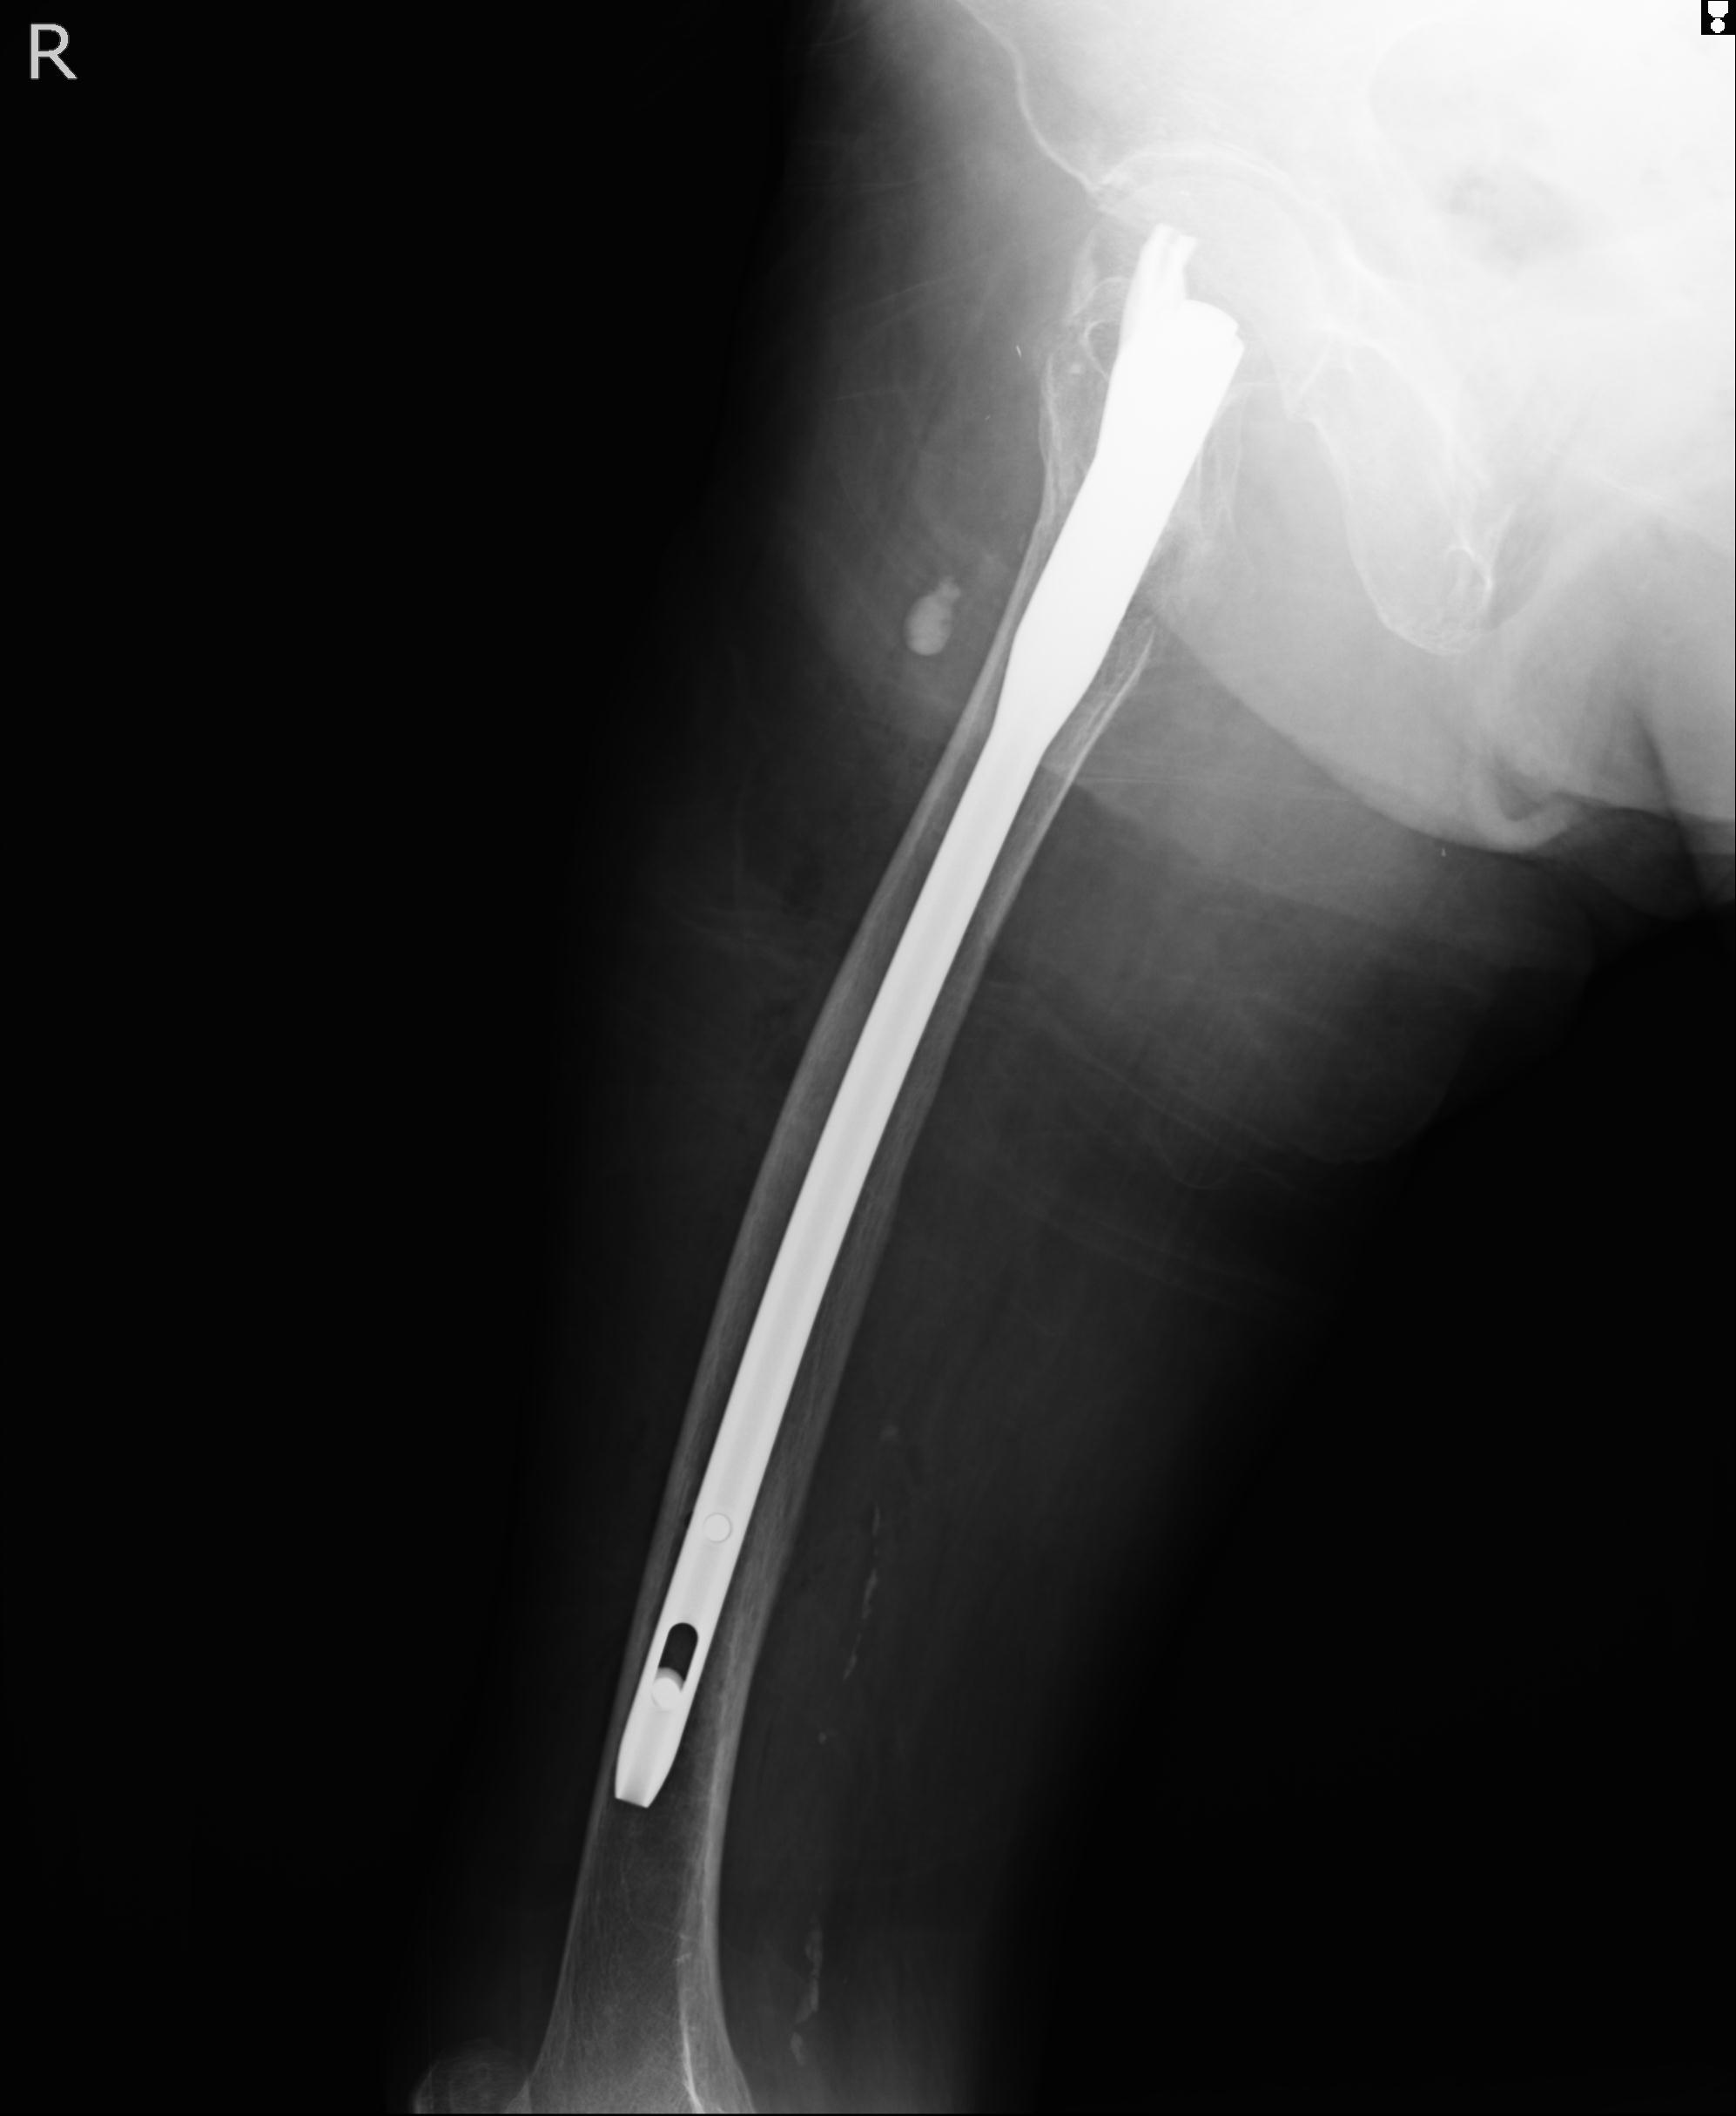

102803 1/12(キウスなし) 1/27 左下腿 4R 30歳女性 左脛骨軸内釘